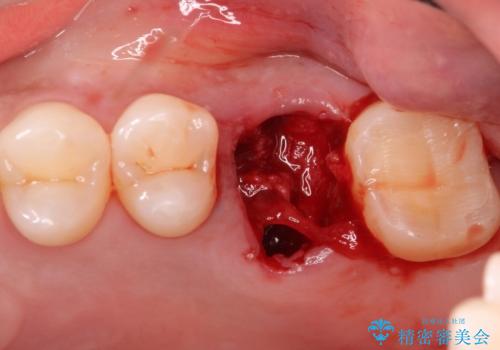

- 左上の奥歯を何とか保存していた患者様です。

今回、残していた歯根から歯茎が大きく腫れ、長期的な予後を期待できないことを考慮し、抜歯してブリッジでの治療を行いました。